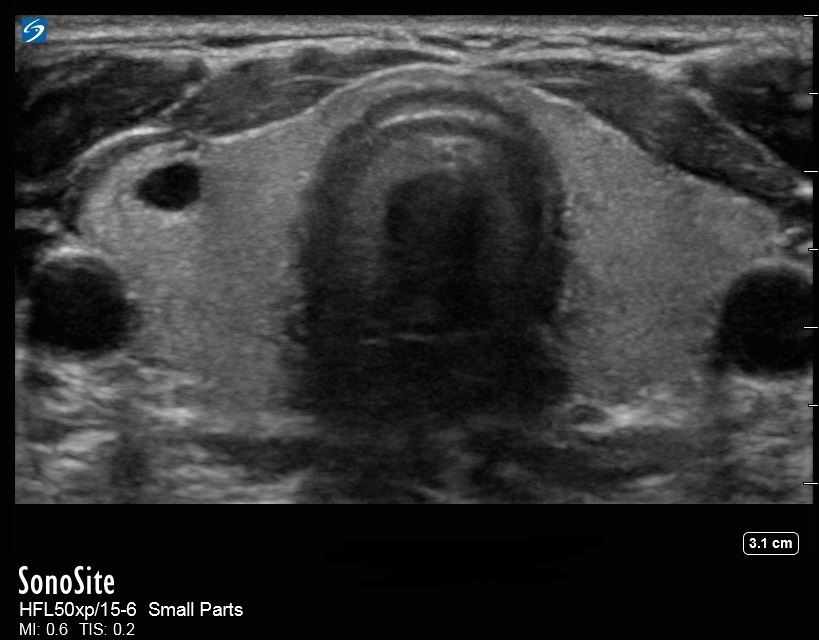

甲状腺嚢胞の画像